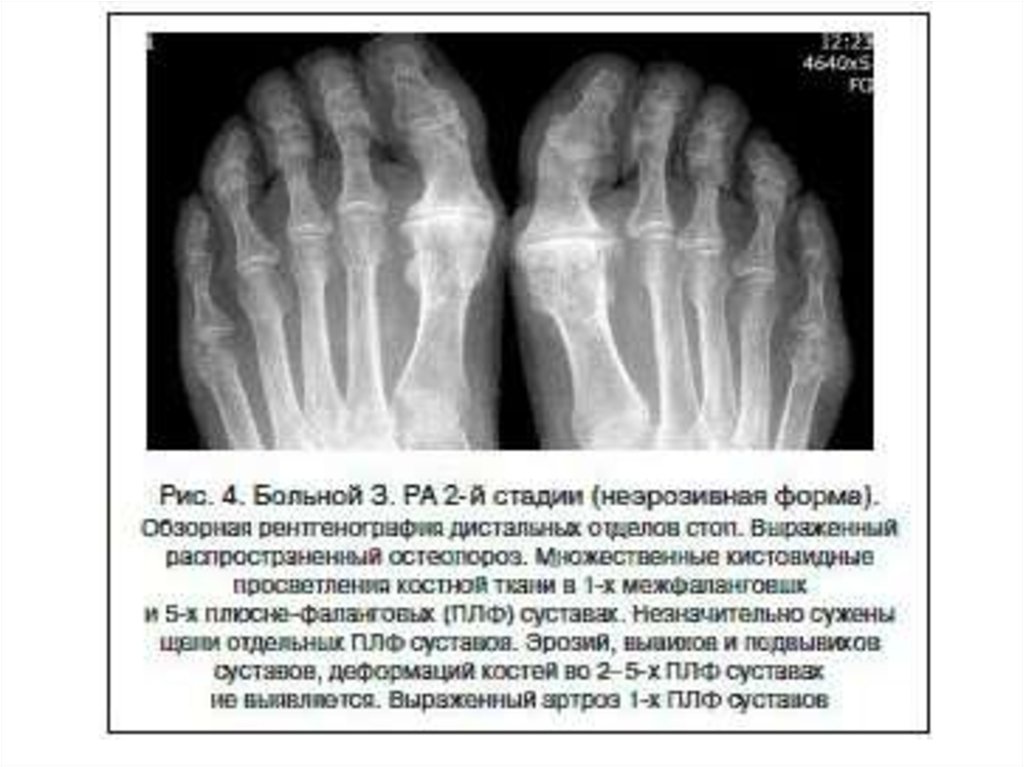

Рентгенодиагностика артрита

1. Рентгенодиагностика артрита